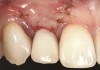

Fig 18. The final restoration after 4 months.

Figure 18